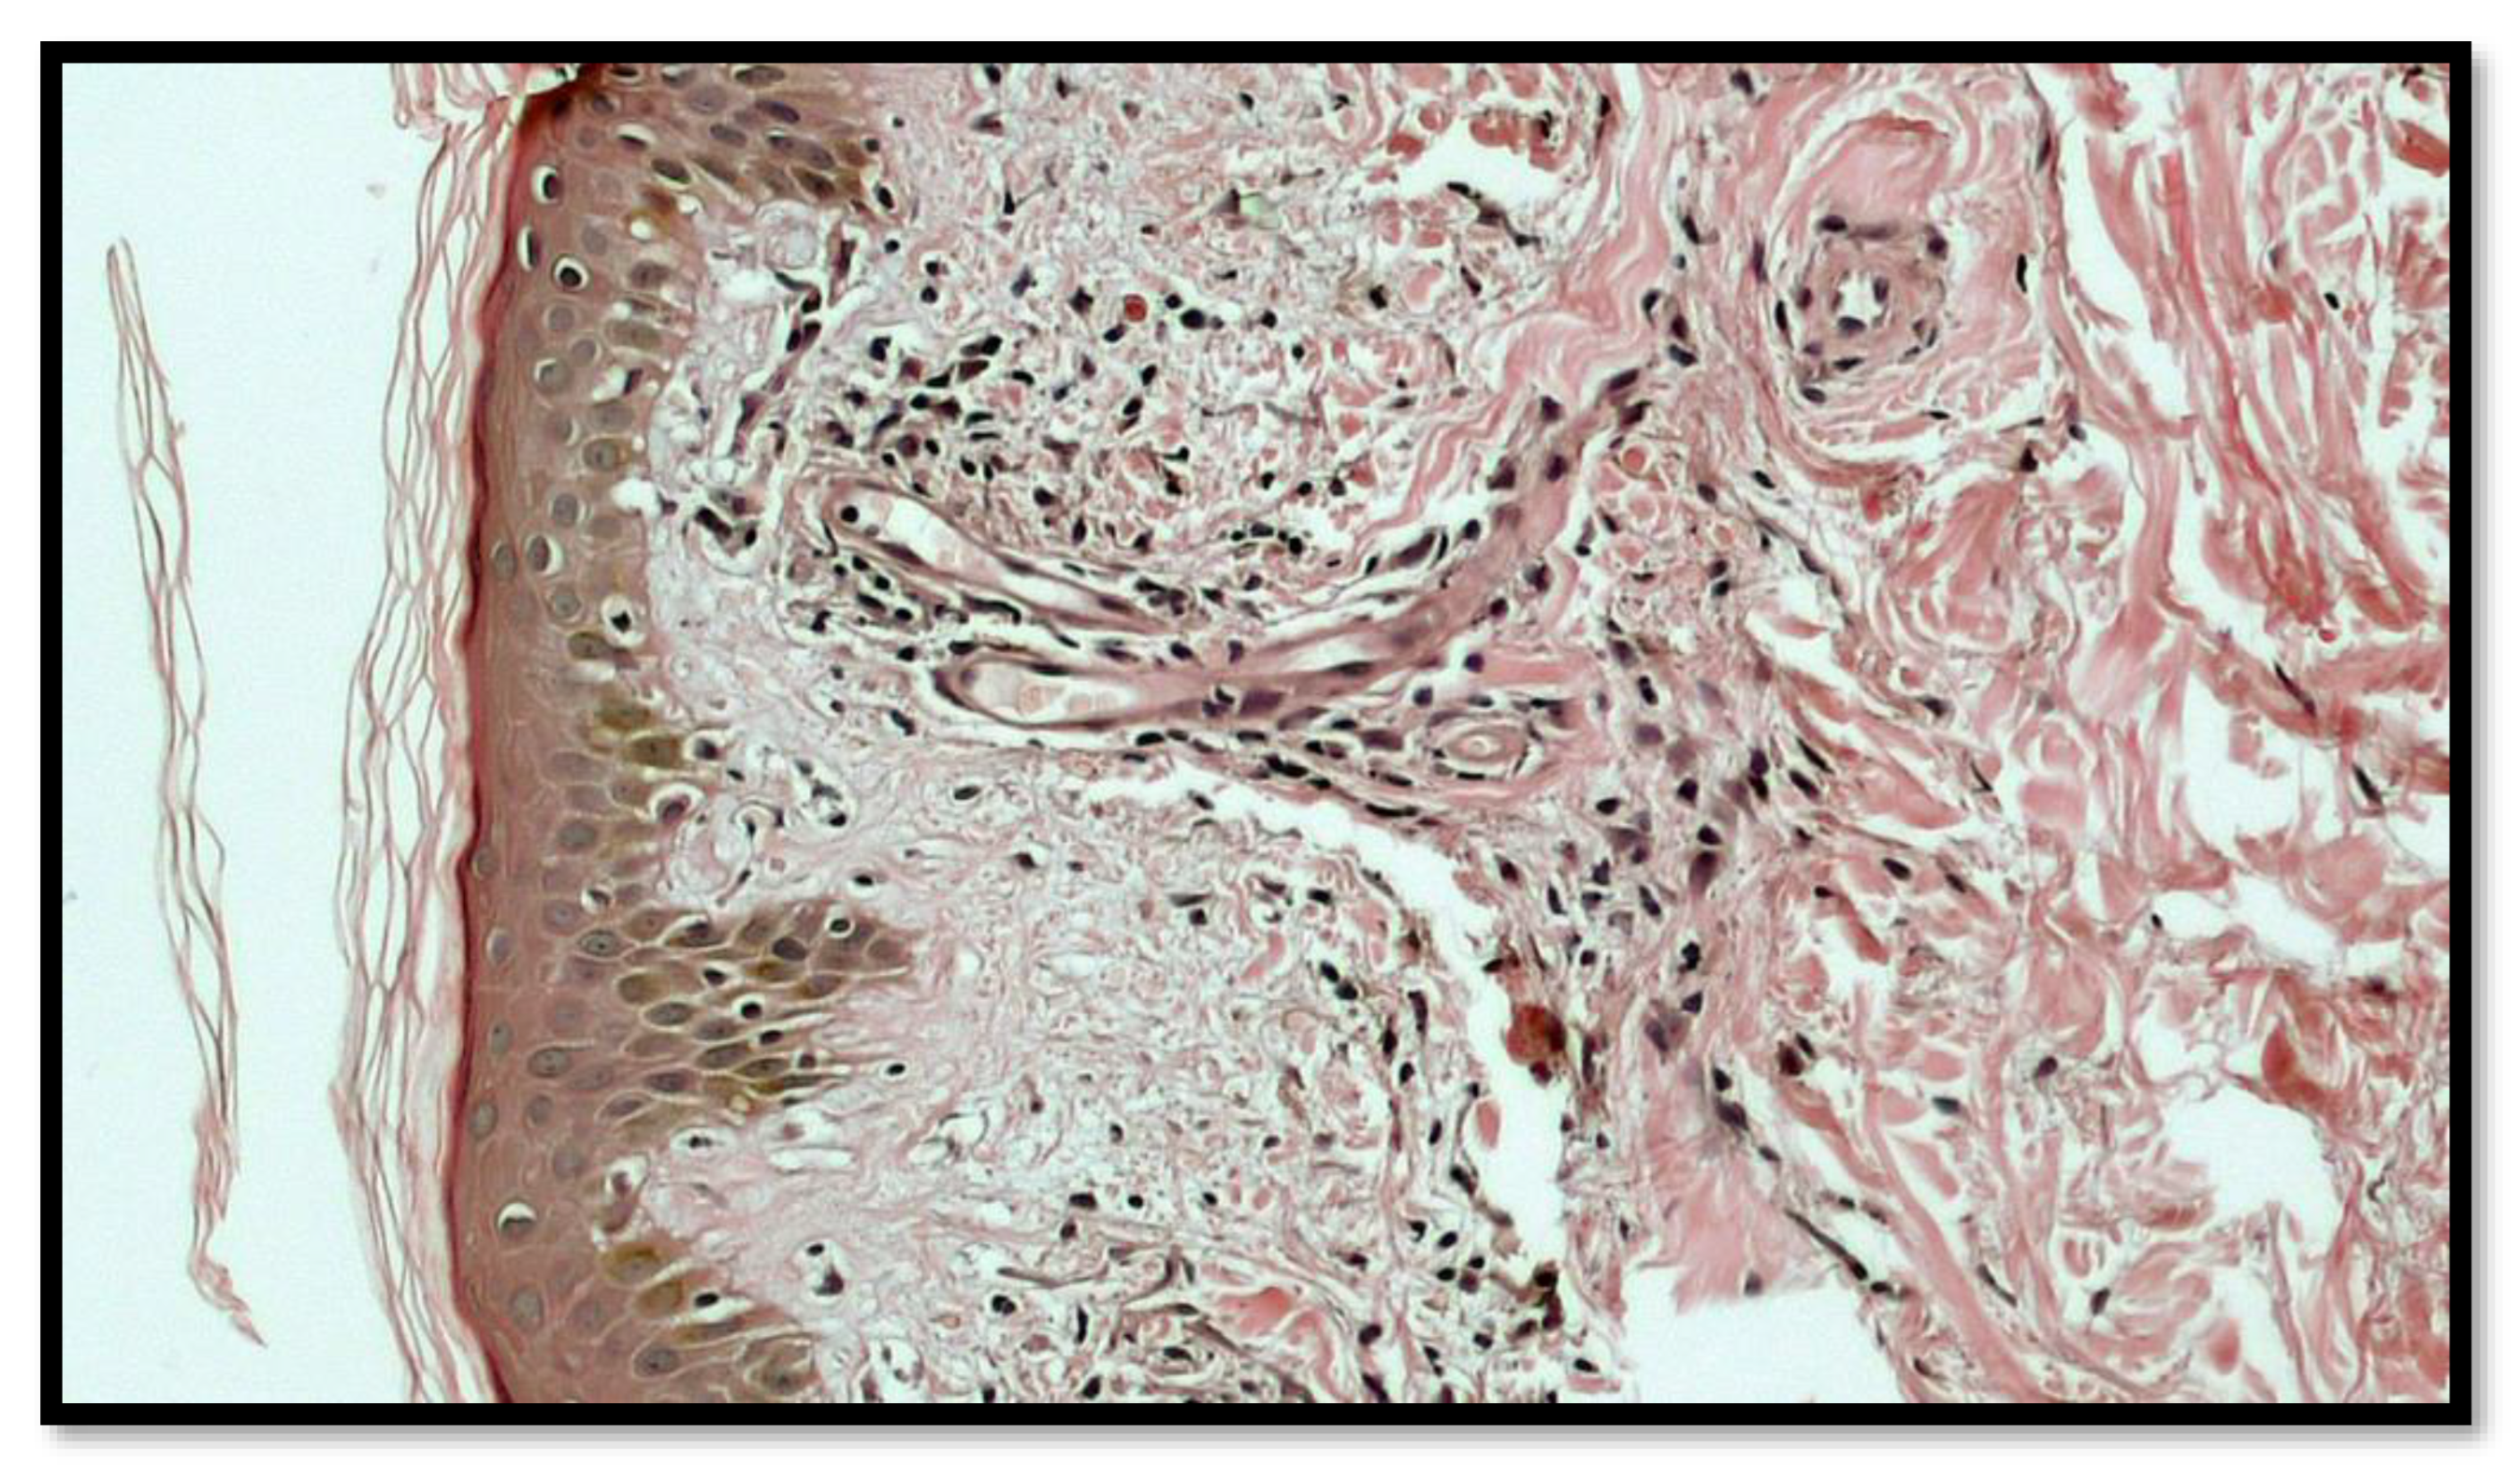

2. Case Report